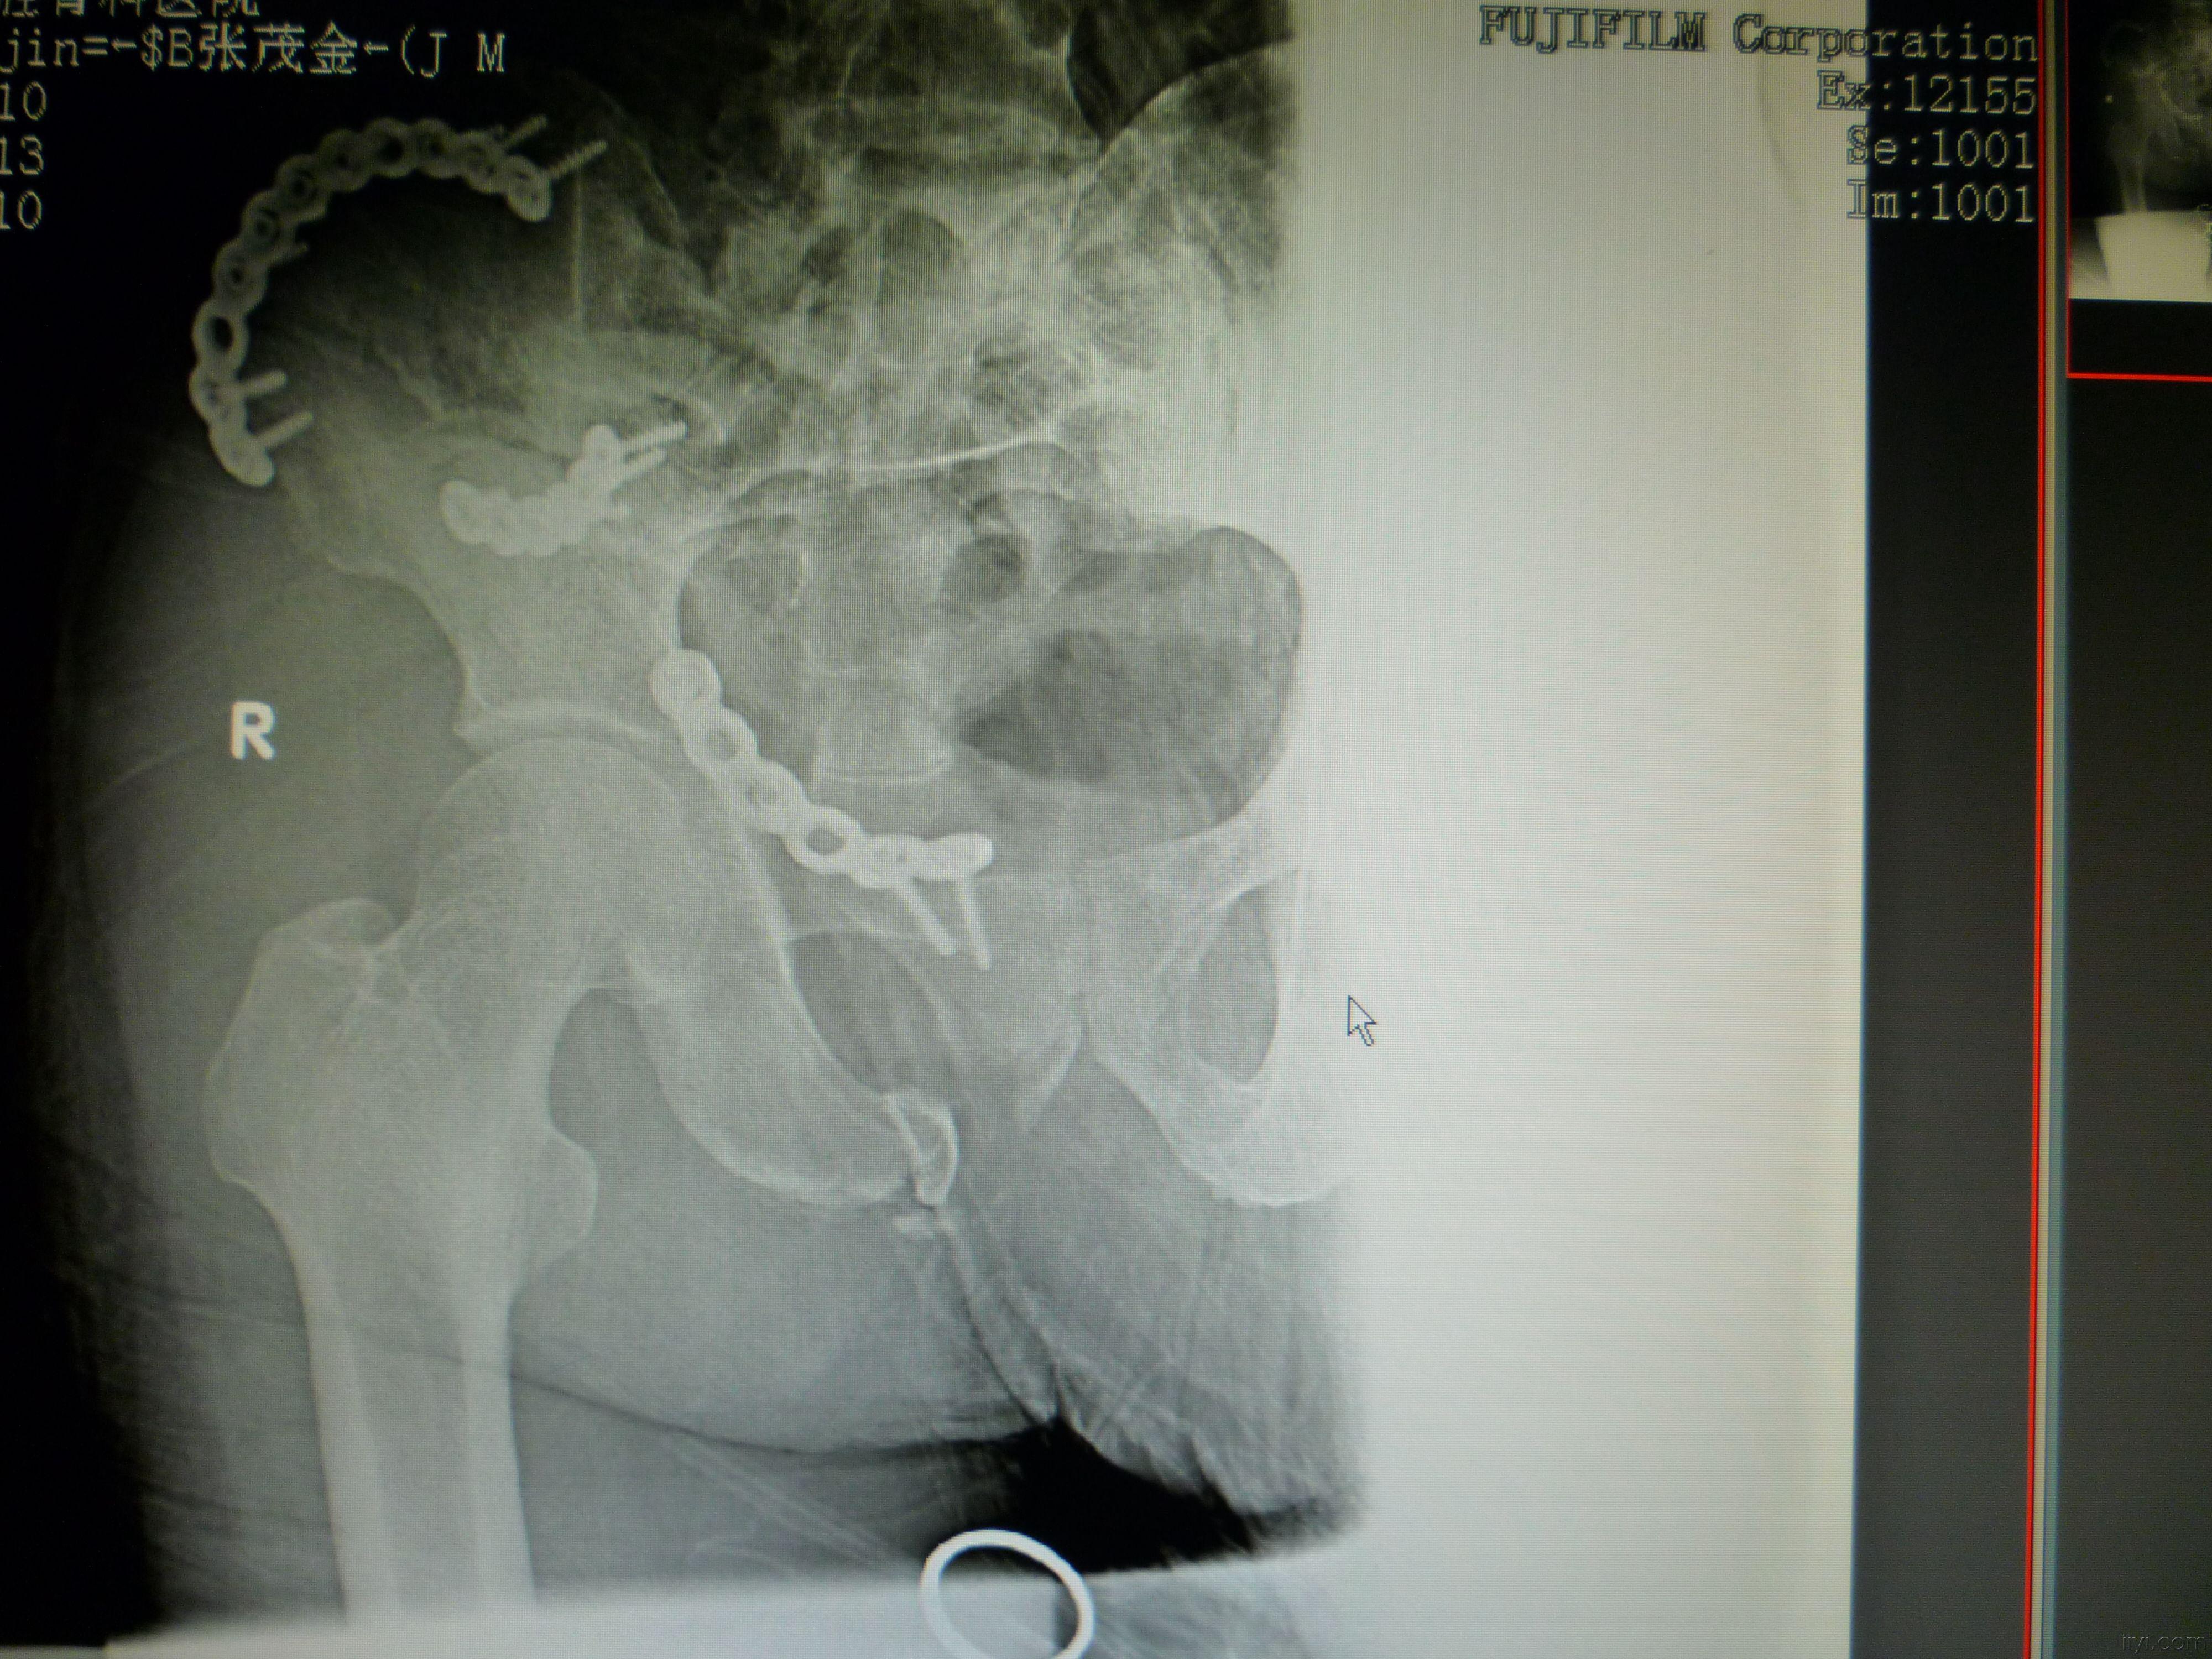

患者男 54岁 车祸伤 骨盆粉碎性骨折内固定

图片尺寸1500x1498